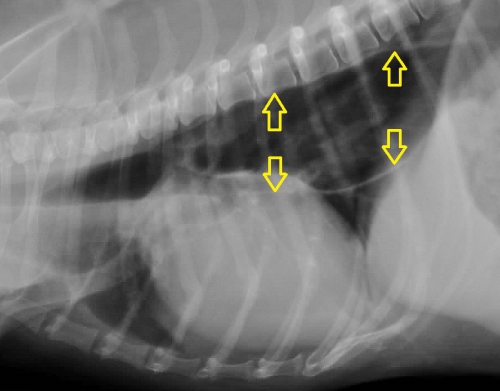

下のレントゲン写真が巨大食道症の一例で、黄色矢印の先に飲み込んだ空気によって拡張した食道壁を示す特徴的な白いラインが見えます。右下が正常の胸部レントゲン写真です。